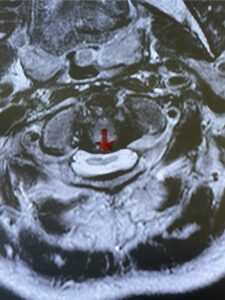

Fig. 4b: Axial T2-weighted cervical MRI demonstrating severe spinal cord compression from atlanto-axial instability (red arrow)

This is a 42 year-old female who presents with severe progressive weakness and numbness and difficulty with balance over a 6-month period. She has a history of having a motor vehicle accident at 5 years old but was never imaged. On exam she was noted to be severely myelopathic. Imaging revealed severe spinal cord compression at the level of C1 (Figs 4a and b).

Cervical x-rays revealed a significantly increased atlanto-axial interval (Fig. 5) On review of her imaging studies it was noted that the right C2 isthmus was very thinned by the vertebral foramen (Figs 6a, b, and c) which would make an attempt at placing a C2 pars screw dangerous. A decision was made to perform an occipital-cervical fusion because only possible unilateral fixation and an extensive C1 laminectomy to be performed eliminating a fixation point if a more traditional C1-C2 was performed. Even if C1 lateral mass screws were able to be placed one could only perform a unilateral screw construct fixation to C2. We performed an occipital cervical fusion down to C4 to get enough inferior fixation and C1 laminectomy. The decompression went well. We placed a left unilateral pars screw and bilateral C3 and C4 lateral mass screws. We placed three 12 mm screws in the midline keel (Fig. 7). Postoperatively the patient had all around improvement in her symptoms and did not qualify for rehab. Her post op films at 6 weeks (Fig. 8)